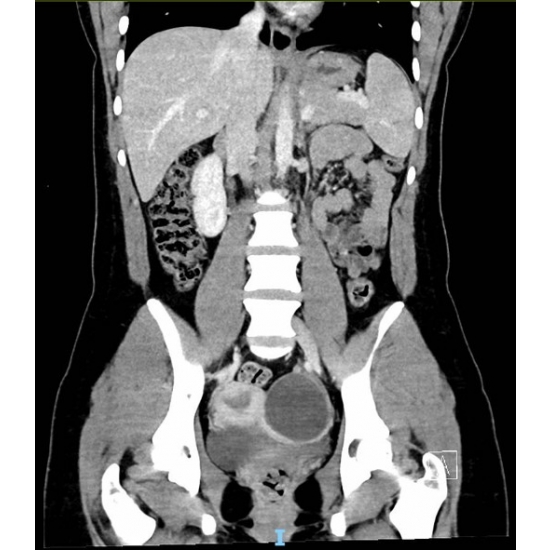

CT Abdomen/Pelvis Case Photo #5 revealed an 8 cm cystic structure in the left adnexa but was otherwise unremarkable.

Neurology was consulted on admission due to the worsening mentation. Hematology/oncology was later consulted for the iron deficiency anemia and recommendations for plasmapheresis. Gynecology was consulted for the ovarian cyst.